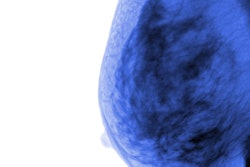

CHICAGO - Digital breast tomosynthesis (DBT) maintains its high performance over time when it comes to decreasing recalls and increasing the cancer detection rate, compared with 2D mammography alone, researchers from the University of Pennsylvania have found.

The study further confirms the technology's place in the breast cancer screening arsenal, according to results presented by Dr. Emily Conant at the RSNA meeting. She and colleagues analyzed DBT screening outcome data from the population level by year and the patient level by round over a six-year period.

"We found that at the population level, that is, everyone who comes for screening in a particular year, DBT increases the overall cancer detection rate and decreases the recall rate compared to 2D mammography, and that this outcome recurs over many years," she told AuntMinnie.com. "At the patient level, we found that successive rounds of tomosynthesis lowered recall rates, improving specificity."